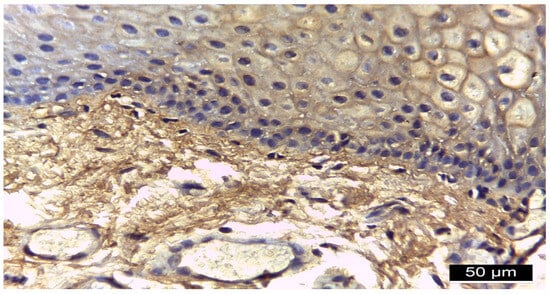

| Patients Number | Diagnostic | Immunoreactivity Intensity CD147 | ||

|---|---|---|---|---|

| Membranous | Cytoplasmatic | Nuclear | ||

| 9 | Diabetes mellitus + Periodontitis | ++ | − | − |

| 7 | Diabetes mellitus + Periodontitis | +++ | − | − |

| 10 | Periodontitis (control) | + | − | − |

| 7 | Periodontitis (control) | − | − | − |

| Location | IR Intensity | DM + PD n = 16 | PD n = 17 | Chi Square Test p |

| CD 147 | ||||

| Membranous | (−) (+) (++) (+++) | 9 (56.2%) 7 (43.8%) | 7 (41.2%) 10 (58.8%) | 0.004 0.001 0.001 0.002 |

| Cytoplasmic | (−) (+) (++) (+++) | 16 (100%) | 17 (100%) | 1.000 nc nc nc |

| Nuclear | (−) (+) (++) (+++) | 16 (100%) | 17 (100%) | 1.000 nc nc nc |